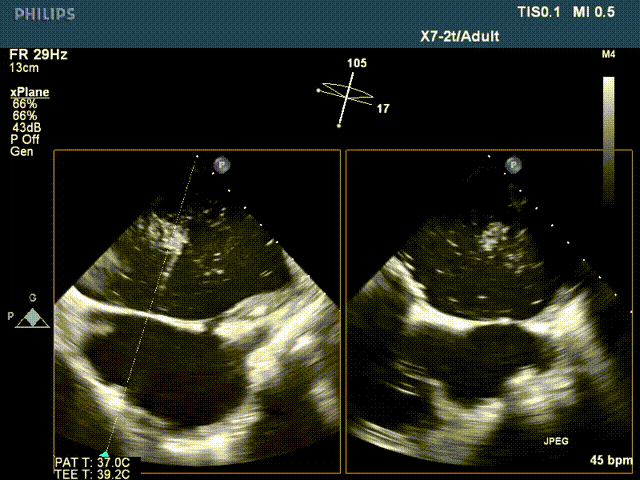

术前超声:

长轴切面二尖瓣狭窄伴关闭不全

三维成像短轴切面观察二尖瓣